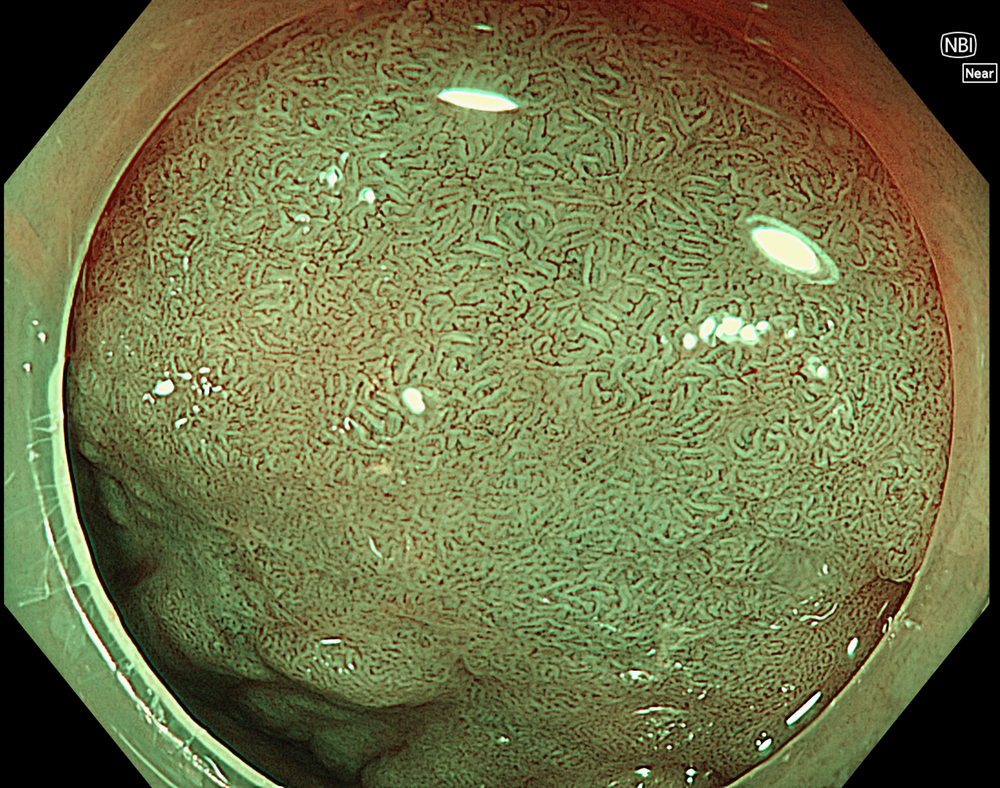

8. NBI with magnification (Near focus)

Magnified NBI with near-focus observation more clearly demonstrates focal irregular surface and vascular patterns, consistent with a JNET type IIb pattern.